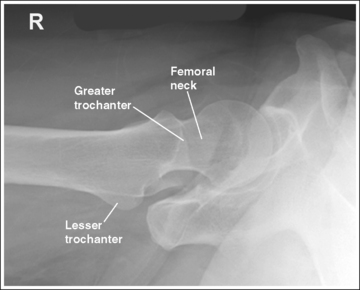

The femoral neck is demonstrated without foreshortening, the greater trochanter is in profile laterally, and the lesser trochanter is superimposed by the femoral neck.

• Accurate leg positioning. To demonstrate an AP hip projection with the femoral neck shown without foreshortening and the greater trochanter in profile, the patient's leg should be internally rotated until the foot is angled 15 to 20 degrees from vertical and the femoral epicondyles are positioned parallel with the imaging table (Figure 7-4; see Figure 7-1). A sandbag or tape may be needed to help the patient maintain this internal leg rotation.

• Poor leg positioning. The relationship of the patient's leg to the imaging table determines how the femoral neck and trochanters are shown on an AP hip projection. In general, when patients are relaxed, their legs and feet are externally (laterally) rotated. On external rotation, the femoral neck declines posteriorly (toward the table) and is foreshortened on an AP hip projection. Increased external rotation increases the degree of posterior decline and foreshortening of the femoral neck on the image. If the patient's leg is externally (laterally) rotated enough to position the foot at a 45-degree angle and an imaginary line connecting the femoral epicondyles at a 60- to 65-degree angle with the imaging table, the femoral neck is demonstrated on end and the lesser trochanter is demonstrated in profile (Figure 7-5; see Image 3). If the patient's leg is positioned with the foot placed vertically and an imaginary line connecting the femoral epicondyles at approximately a 15- to 20-degree angle with the imaging table, the lesser trochanter is demonstrated in partial profile and the femoral neck is only partially foreshortened (see Image 4).

• Positioning for a fractured or dislocated proximal femur. When a patient has a dislocated or fractured proximal femur, the leg should not be internally rotated but left as is. Forced internal rotation of a dislocated or fractured proximal femur may injure the blood supply and nerves that surround the injured area. Because the patient's leg is not internally rotated when a fracture is suspected, the resulting AP hip projection may demonstrate the femoral neck with some degree of foreshortening and the lesser trochanter without femoral shaft superimposition (see Image 5).